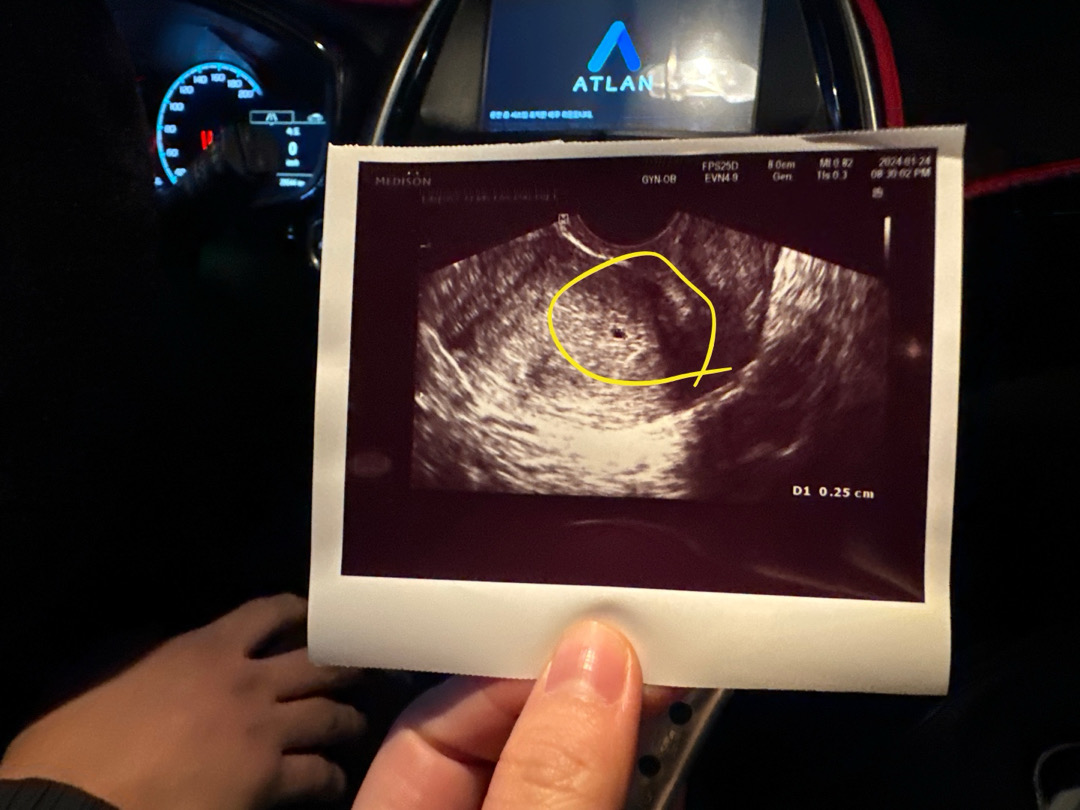

주수는 5주1일 인데 4주 5일에 애기집 확인 했는데.. 아기집이 작다고 하는데… 많이 작은가요?? 4주5일 확인했을때0.25 였어요… 그리고 오늘 약간? 갈색냉? 혈? 비슷한게 조금 나오긴 했어요…ㅠㅠ 목요일에 병원 가는데 괜찮을까요?

크기가 작은거보단 하루에 커야하는만큼(1mm) 자라는게 중요하다고 하더라구요 저도 0.29? 정도여가지고 산부인과선생님이 아기집일 확률이 90프로다 이런식르로 말하셨는데 며칠뒤에 가니 정상적으로 잘 크고있다고 임신확인서도 주셨어여 오늘은 심소들었어여! 걱정할수록 시간만 안가는거같아요 좋은생각만 하세여❤️

4주5일에 0.42였는데 5주차에 가니깐 0.7이고 일주일씩 가도 다르더라구요😀 그리고 걱정되시면 병원 바로 가보시는게 맞는거같아요!